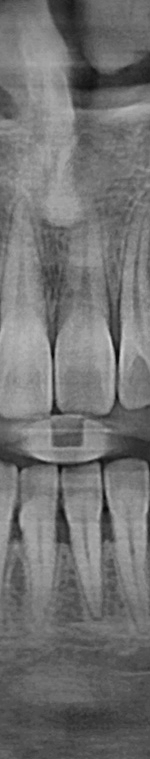

사랑니발치를 하기 위해서는 먼저 파노라마 x선 사진을 통해 발치 시 신경에 영향을 줄 수 있는지 확인하는 과정을 진행했어요. 이 과정을 통해서 충분히 의사와 상담을 한 후 처방전을 발급했어요. 이 때 처방전에는 항생제를 포함하여 발치 후 통증을 대비한 진통제를 처방했어요. 환자에게 충분히 설명한 후에 국소마취를 진행하고 마취가 된 다음에 절개를 최대한 덜 하는 방향으로 수술하여 사랑니를 발치했어요.

턱 뼈와 치아 사이에 공간이 충분하지 않기 때문에 누워서 올라오거나 매복되어 자라는 경우가 많았어요. 반포치과를 찾는 분들의 사랑니의 경우 매복된 경우도 많고 이가 완전히 잇몸 밖으로 나오지 않아서 일반 치과에서는 발치가 어려웠어요. 사랑니발치가 왜 필요한지 가끔 의문을 가지는 분이 계셨어요. 사랑니발치를 왜 해야 하는지 알려드리겠어요. 사랑니는 다른 치아처럼 바르게 나는 경우도 드물게 있긴 하지만 대부분 어금니 쪽으로 기울어져서 올라오거나, 완전히 수평으로 누워서 자라는 경우도 있었어요. 누워서 자라는 치아는 옆의 치아를 밀어 치열이 비뚤어지고 부정교합을 유발했어요.

사랑니가 90도로 누워서 난 경우는 수평 매복, 뼈나 잇몸에 사랑니가 완전히 덮여서 아예 보이지 않는 경우는 완전 매복, 일부분만 잇몸이나 뼈에 덮여있는 경우 부분매복이라고 했어요. 대부분의 환자분이 이런 매복 중에 한 가지에 해당하기 때문에 시술이 매우 어려웠어요. 특히 사랑니 주변으로는 구강과 관련된 중요한 신경 조직이 인접하여 있기 때문에 고난이도 시술이라고 할 수 있었어요.